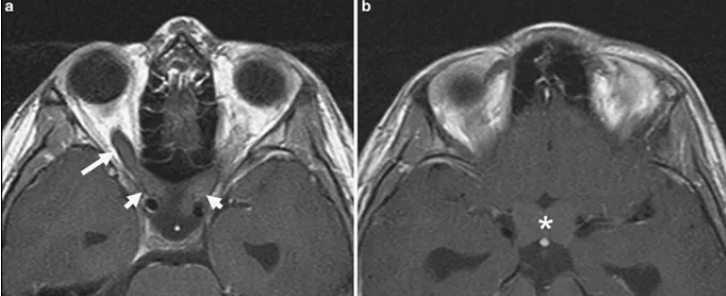

视神经胶质瘤会导致失明吗?INC国际神经外科专家指出,虽然视神经胶质瘤通常被归类为良性的低等级WHO(国际卫生组织)1级毛细胞星形细胞瘤,一般很少进展到高等级。但视神经胶质瘤由于生长在视神经上,随着缓慢的增大,会不断影响孩子的视力,较终可能导致失明。视神经型胶质瘤在临床上典型的表现为早期出现视力逐渐下降、视野缺损,随着病变体积增大,出现眼眶占位性病变的特点,即进行性眼球突出、眼球运动受限、斜视等,故视力下降先于眼球突出出现。在婴幼儿期的视神经胶质瘤多表现为眼球震颤和斜视。特别是儿童出现视力下降时因其主诉不明确,往往在出现明显的眼球突出或因视力丧失导致废用性斜视时被家长发现才就诊,故儿童患者就诊时视力损伤已很严重甚至失明。

视神经胶质瘤能治好呢,手术切除会导致失明吗?任何疾病,只要沾上一个瘤字,都不是容易治疗的,视神经胶质瘤也一样,即使国际卫生组织(WHO)将其归为I级良性肿瘤。对于进展性视神经胶质瘤的治疗可通过化疗、放射治疗或外科手术进行,一般手术切除是更佳的选择。但由于视神经胶质瘤位于颅内,周围血管环绕,布满重要神经组织,所以手术难度是高的,手术不仅难以取得高切除率,而且还可能导致孩子失明。但是想要使视神经胶质瘤预后更好的话,是需要确定一个手术高切除率的。手术切除率一般只要高于90%,再次复发的几率较低,但是要在不损伤周围神经组织及要保留患者视力的情况下,达到高切除率对医生是一个较大的挑战,考验医生的技术和其手术经验。这也是为什么国内的医院建议前文的小孩采取保守治疗。